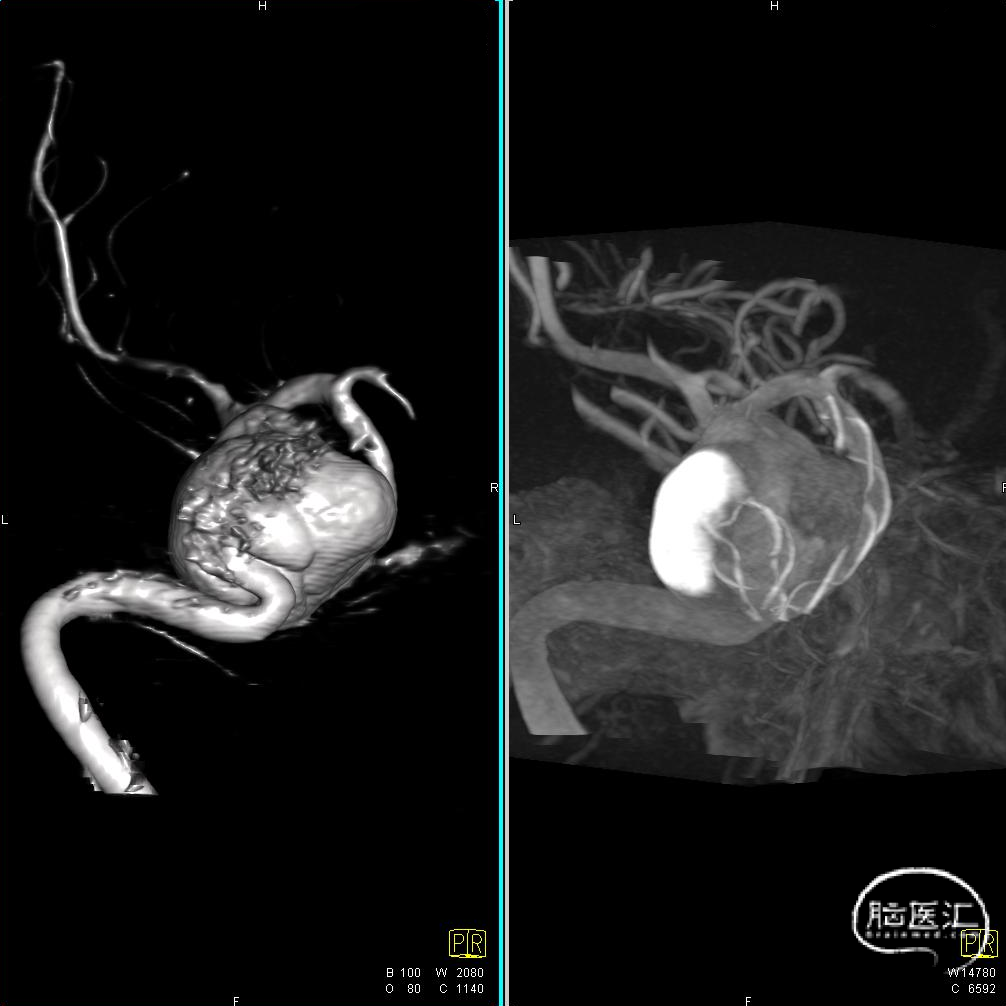

术前CT检查显示,可见左侧侧裂内侧类圆形高密度。

DSA造影显示为左侧颈内动脉海绵窦段巨大动脉瘤。

通过3D工作位测量出左侧海绵窦段动脉瘤尺寸:33mm不规则动脉瘤,载瘤动脉尺寸:近端直径4.55mm,远端直径3.97mm。

造影后发现该患者左侧海绵窦段动脉瘤,动脉瘤不规则,最大径33mm,未破裂,不累及分叉部,动脉路径迂曲。

患者为左侧海绵窦段动脉瘤,载瘤动脉段虽然有弧度,但也算平坦,符合血流导向装置释放条件,计划直接释放密网支架。